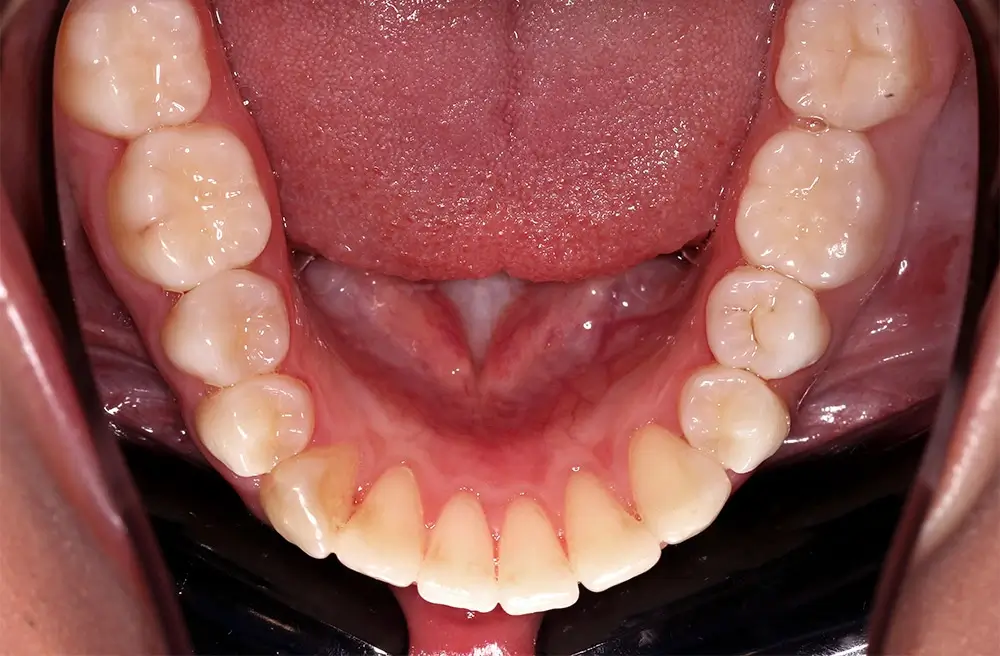

Скученность - Кейс 10

Эффективность устранения дефекта прикуса посредством элайнеров FlexiLigner.

16

Количество кап НЧ

Количество кап ВЧ

Результаты лечения